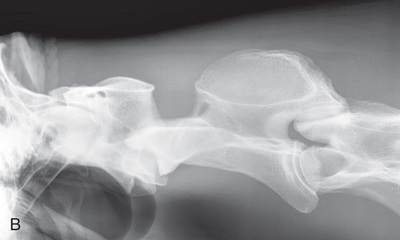

| Cervical spine | Lateral (Fig. 24.58) | Side of the cervical region. | Opposite side of neck. | Centered on region of choice: | Because of the size of the patient, the cervical spine must be exposed in three views. The patient can be standing or recumbent. |